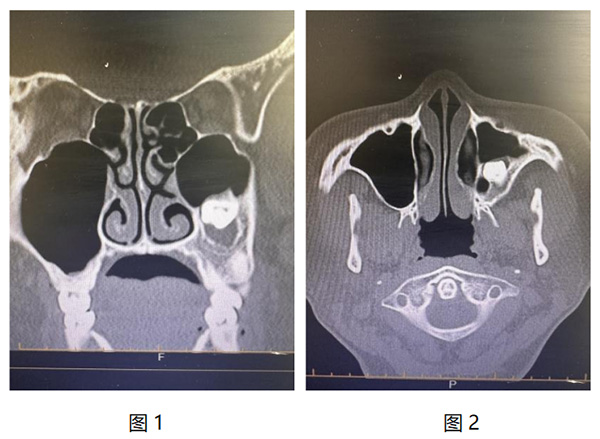

近日(ri),我(wo)院耳鼻咽喉頭頸外科(ke)成(cheng)功爲(wei)一(yi)名(míng)特殊病症患者實施了(le)高(gao)難度手術(shù)。患者因“牙片檢(jian)查時髮(fa)現(xian)上颌窦阻生(sheng)齒伴囊腫形成(cheng)1月”入院,經(jing)鼻窦CT檢(jian)查,可(kě)見其左側上颌窦內(nei)存在(zai)高(gao)密度影,且周圍有(yǒu)軟組織包繞,診斷(duan)爲(wei)上颌窦阻生(sheng)齒伴囊腫形成(cheng)。(圖1、2)。